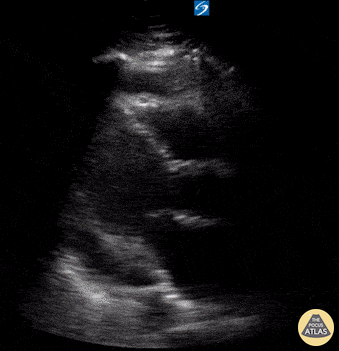

Seen here is a circumferential pericardial effusion identified in a patient without hemodynamic evidence of tamponade. Moudi Hubeishy @moudihubeishy